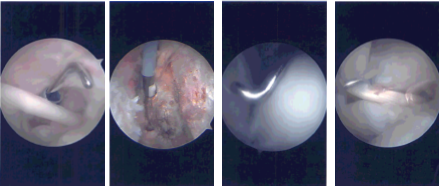

The arthroscope was inserted into the glenohumeral joint where examination showed fraying of the lateral part of the subscapularis tendon, fraying of the anterior and posterior labrum, grade 1 to grade 2 lesion of the cartilage of the glenoid head, fraying and partial tearing of the rotator cuff on the articular side.

Debridement was done with the use of shaver for the glenoid labrum, subscapularis tendon, articular cartilage of the humeral head as well as the rotator cuff. The arthroscope was inserted in the subacromial space. Examination showed partial freeing of the rotator cuff along the supraspinatus.

There was lateral anterior spurring of the acromion as well as AC arthritis. Shaver followed by a Coblation wand was used to clear up the acromion as well as the AC joint.

Repair of the rotator cuff tear was performed with the use of a small Regeneten implant, which was put in place with the use of multiple tacks through lateral and the accessory superior portal. Pictures were taken for the draft.

Intraoperative Arthroscopy Images

Acromioplasty was performed with the use of a #6-0 bur followed by distal clavicular excision by removing about 1 cm of the distal clavicle through the posterior and followed by the anterior portal. All the pictures were taken and saved.